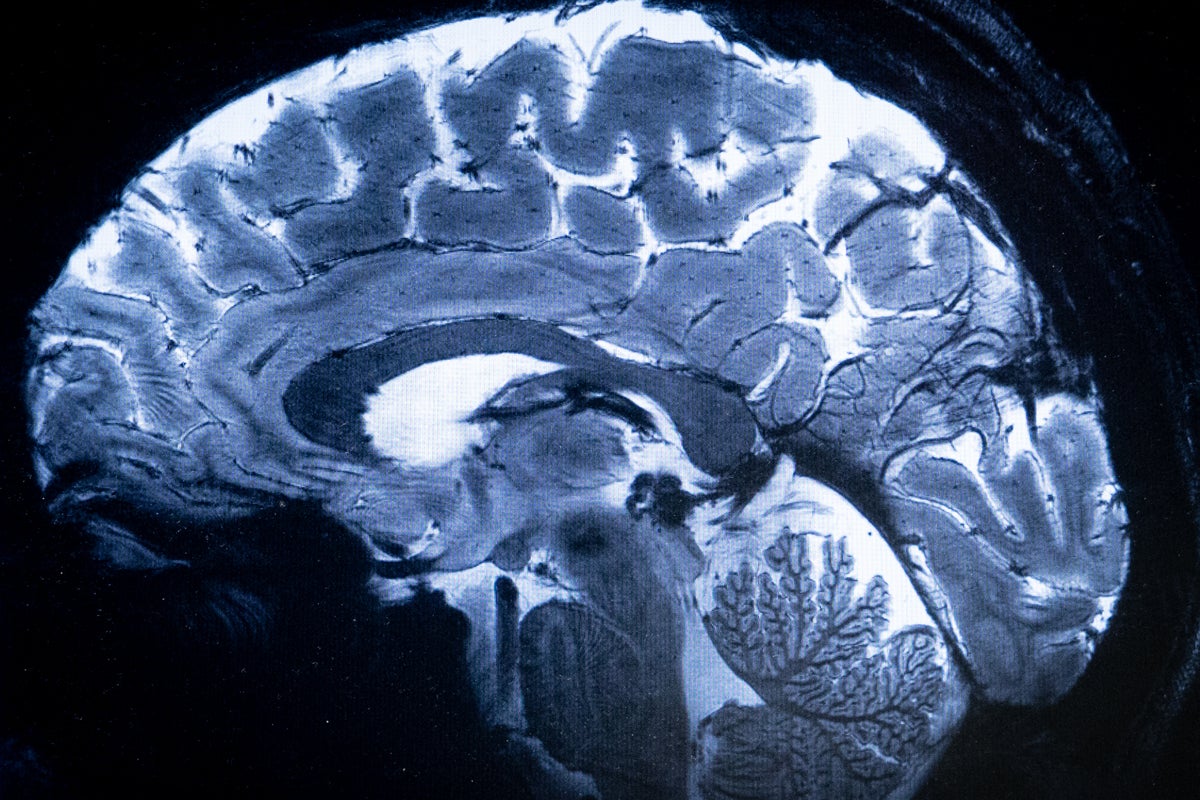

"Brains with any of the four conditions tended to have a reduced surface area in regions responsible for processing emotions, responding to threats and maintaining awareness of bodily states. The University of Bath conducted the largest international study of its kind and analysed brain scans from around 9,000 children and young people, with approximately half of them diagnosed with a mental health condition."

The University of Bath analysed brain scans from about 9,000 children and young people, roughly half diagnosed with a mental health condition. Young people with anxiety, depression, ADHD and conduct disorder shared similar structural brain changes. Brains with any of the four conditions showed reduced cortical surface area in regions involved in processing emotions, responding to threats and maintaining awareness of bodily states. The findings were published in Biological Psychiatry and suggest mental health disorders should not be studied in isolation. Simultaneous analysis of multiple conditions may enable treatment strategies that address overlapping neurobiological features.